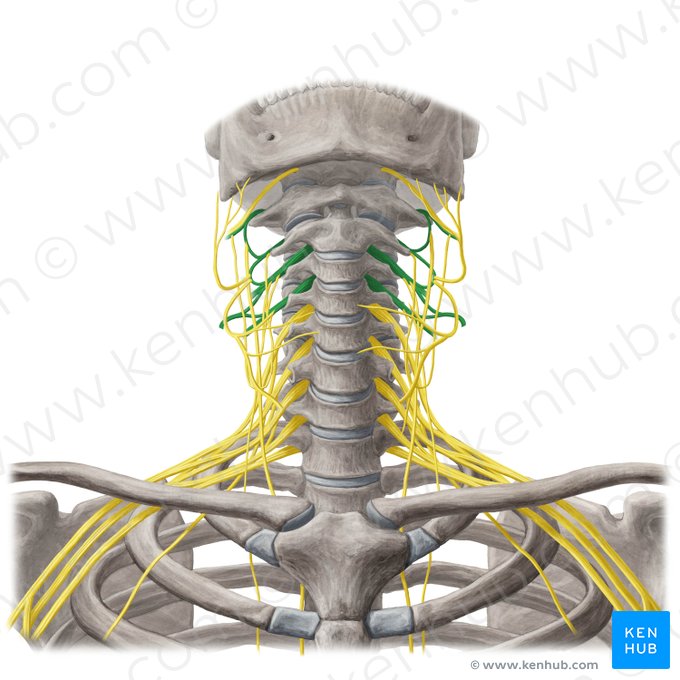

cervical plexus

C1-C4

major nerve: phrenic nerve

brachial plexus

C5-T1

major nerves: “rum in the am”

segmental branches

hypoglossal nerve (12)

lesser occipital nerve

greater auricular nerve

transverse cervical nerve

ansa cervicalis

accessory nerve (11)

phrenic nerve

supraclavicular nerves

axillary nerve

radial nerve

musculocutaneous nerve

ulnar nerve

median nerve